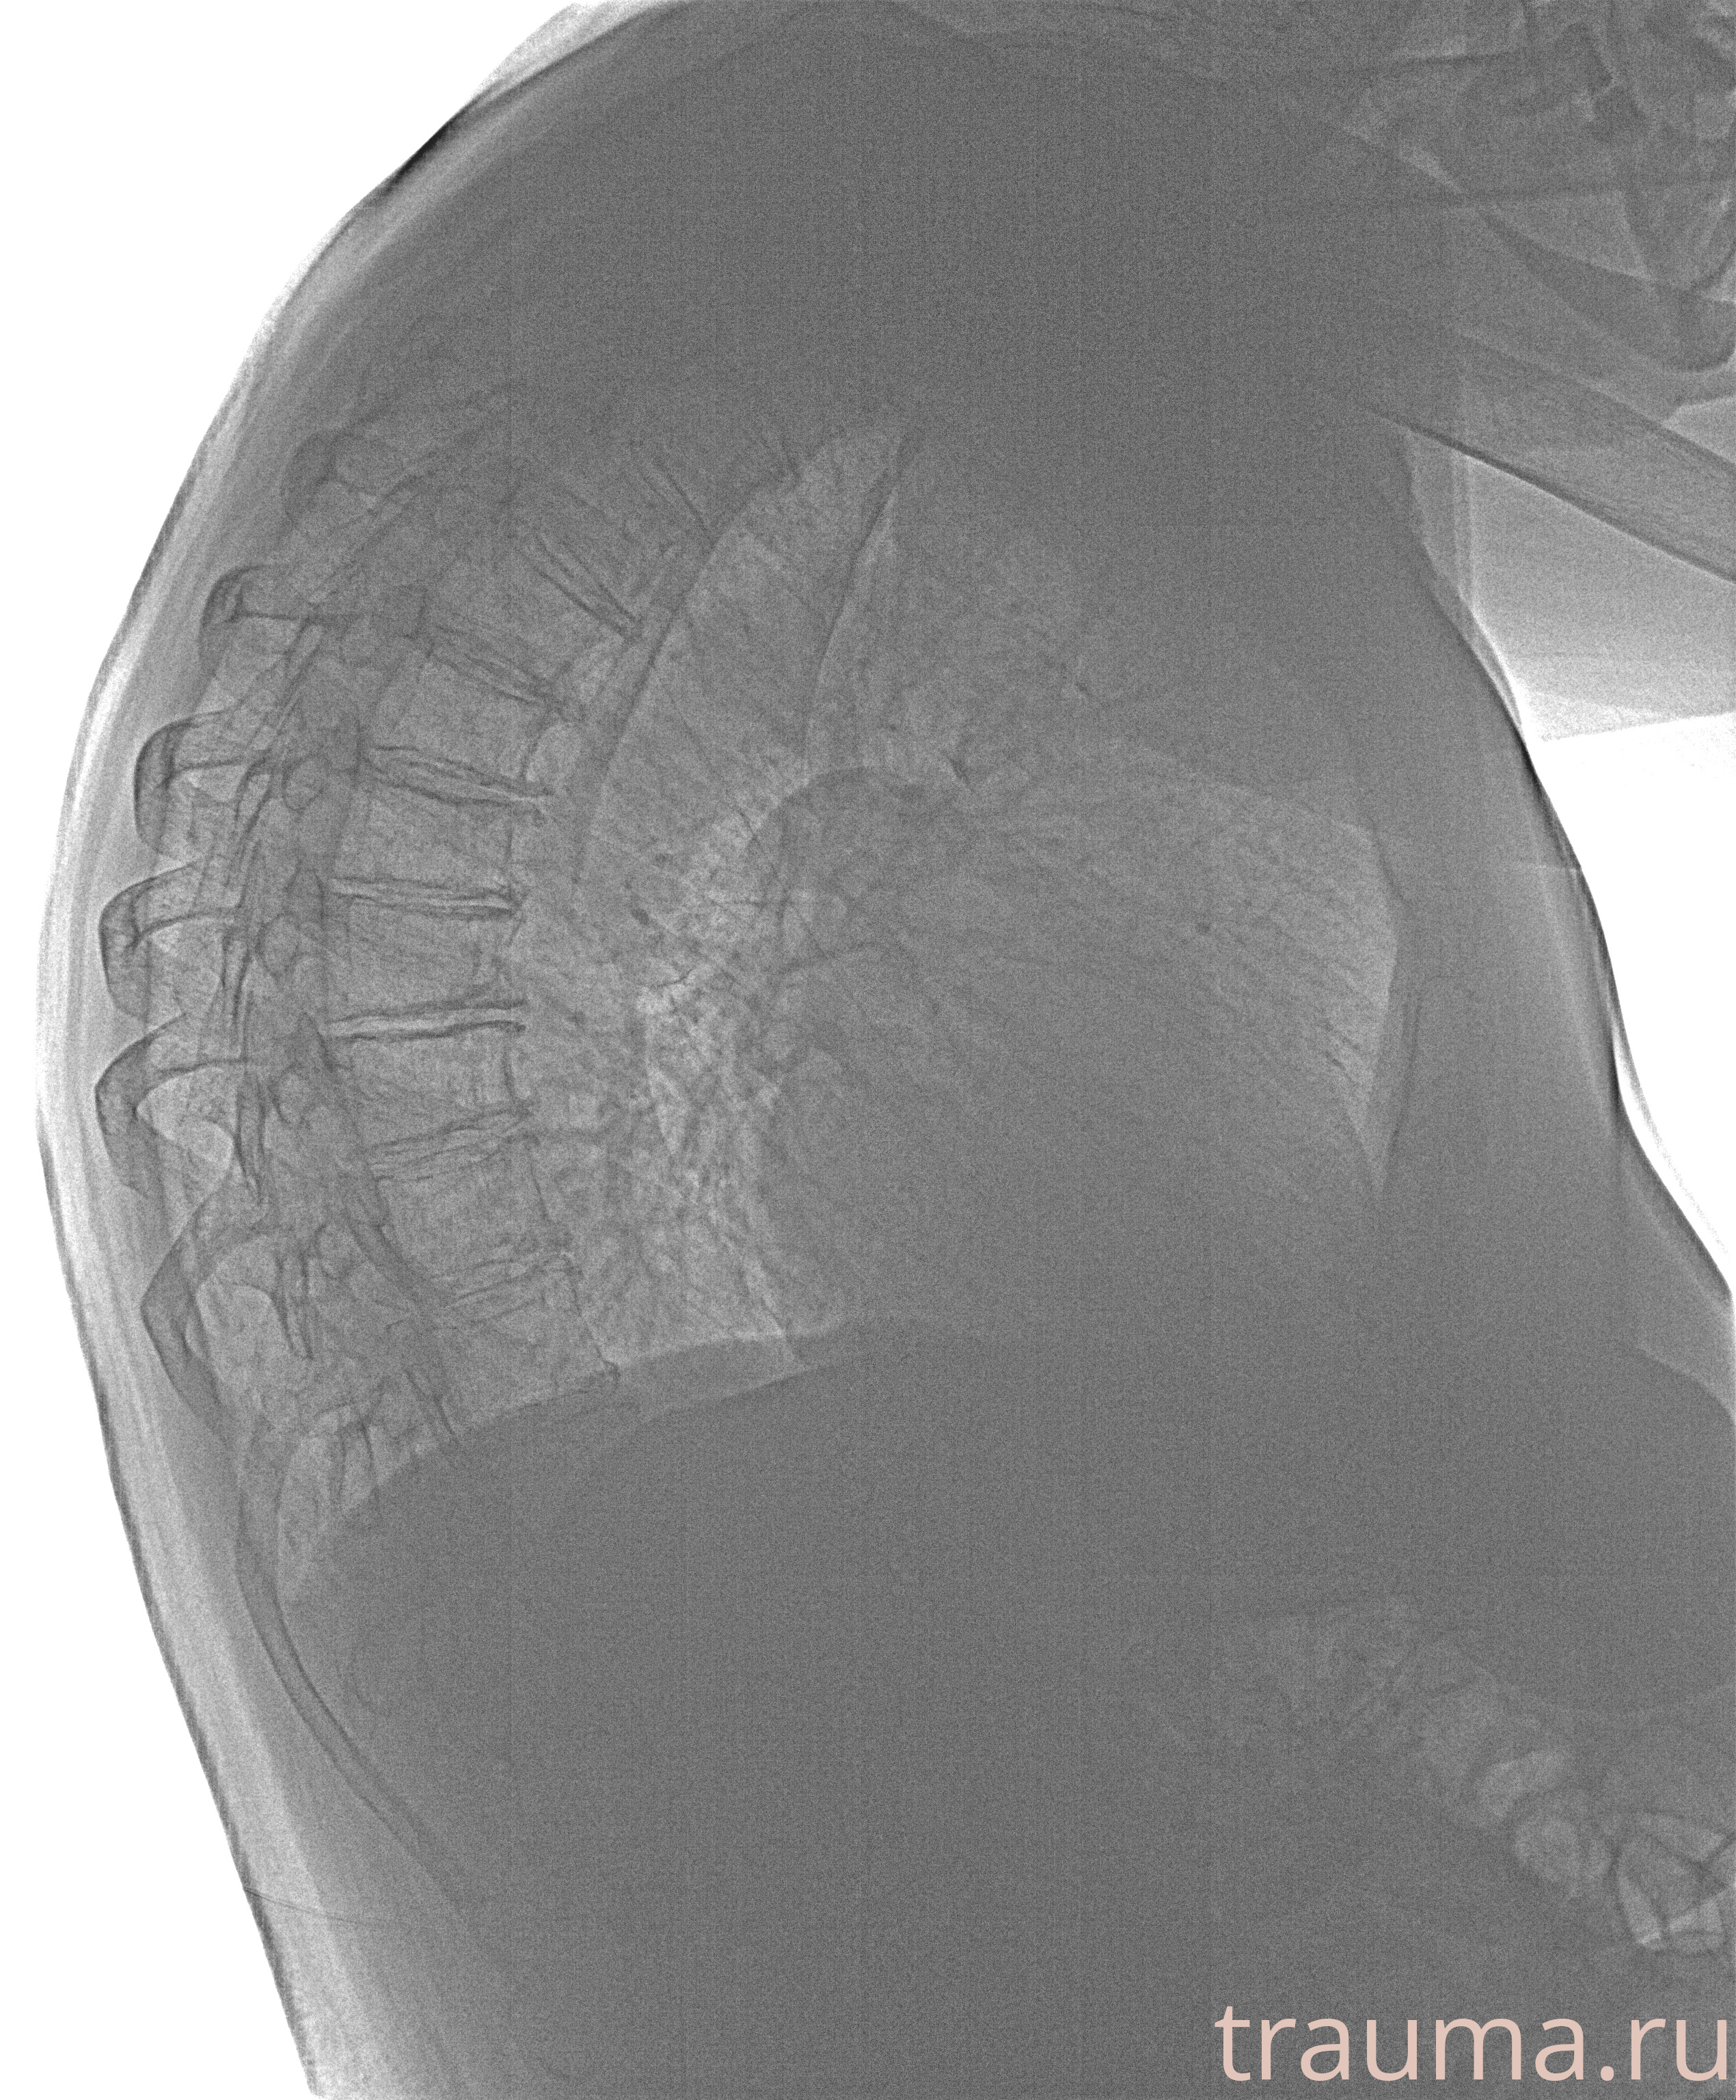

Рентгенограммы

Рентген на дому: по вашему адресу приезжает врач-рентгенолог, травматолог-ортопед с мобильным рентгеновским аппаратом, проводит диагностику травмы или заболевания, делает необходимые рентгенограммы, дает рекомендации по дальнейшему лечению. Получить качественные снимки в домашних условиях возможно благодаря уникальной методике, разработанной МосРентген Центром для института  Склифосовского

при переломе шейки бедра и пневмонии от компании МосРентген Центр - партнера Института имени Склифосовского